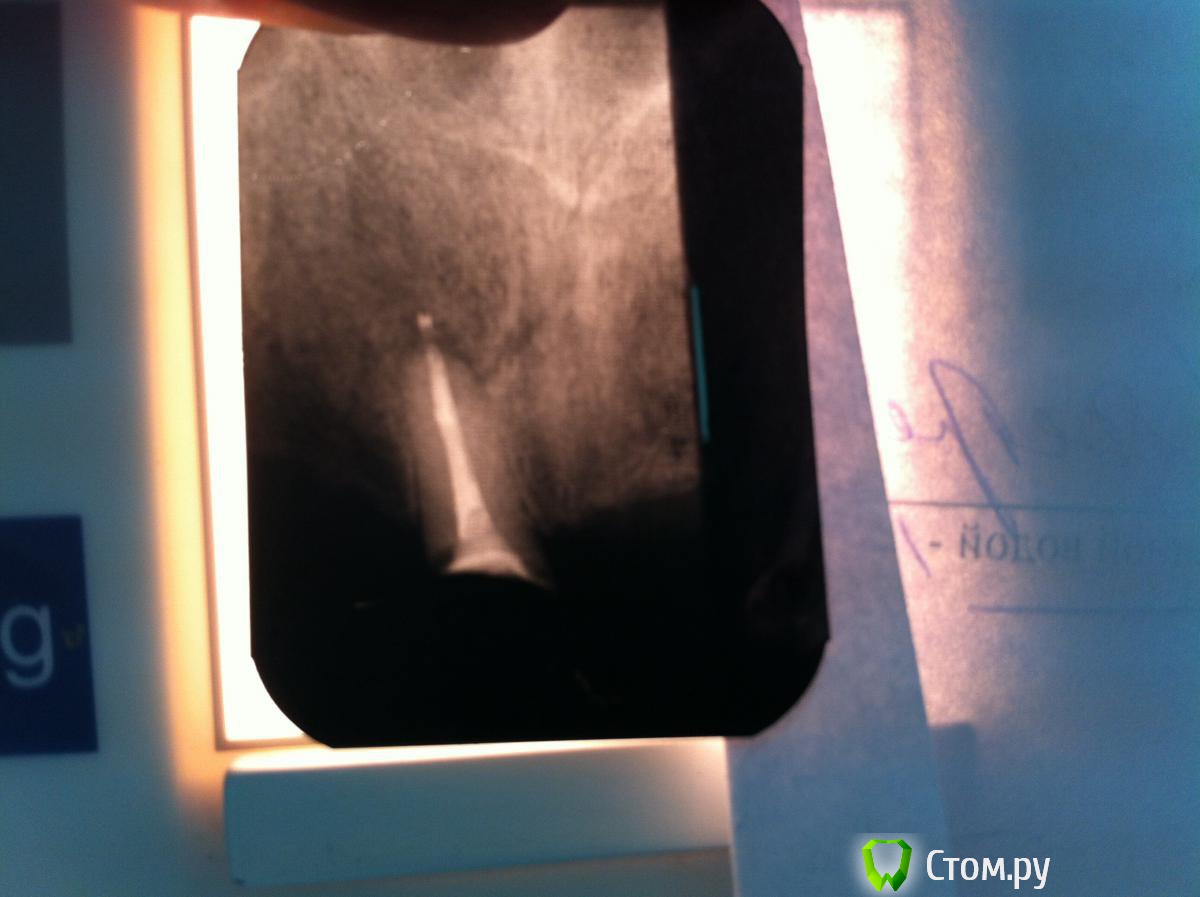

M@estro Опубликовано 1 декабря, 2013 Автор Поделиться Опубликовано 1 декабря, 2013 Недавно тема была про апексы, Гер Берра создавала, не в бровь - а в глаз : http://s020.radikal.ru/i723/1312/d9/13699f1a65de.jpg Зуб 2.6,4 месяца назад была попытка сохранения "витальности",вскрыт в 1 точке,закрыт мта, симтоматики никакой за неделю не проявилось,реставрировали. Пришел 2 недели назад - жалобы на боли (холодное) . Эод,депульпируем, в первое посещение - первичная обработка , кальций. Во второе посещение найден мб 2,патенси не получил,обработал на 17 миллиметров(мб1 21 мм), нёбный 26 мм Получил в нёбном "сюрприз" 9 Ссылка на комментарий